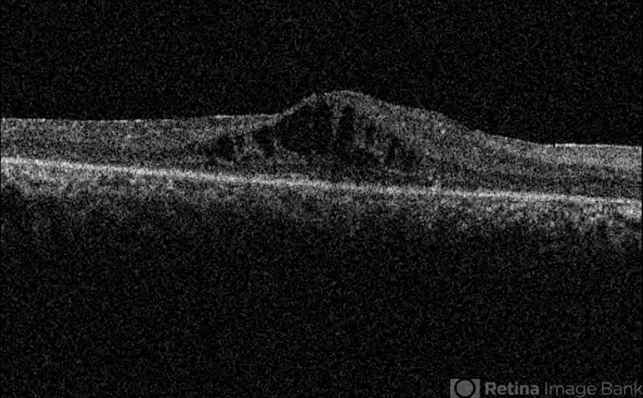

- cystoid macular edema (CME), retinitis pigmentosa, optical coherence tomography (OCT)

- Topcon OCT

- OCT image of the right eye of a 30-year-old woman with cystoid macualr edema due to retinitis pigmentosa.